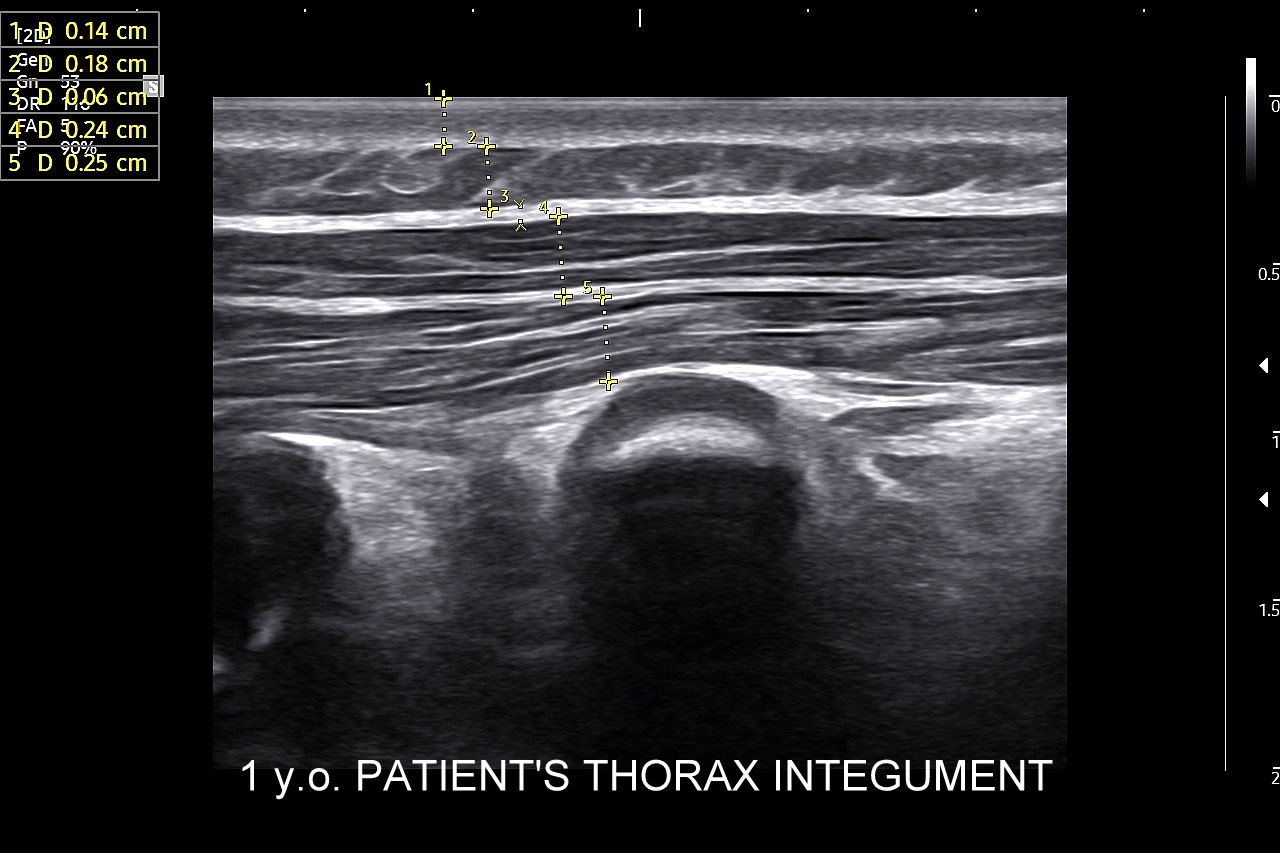

Ultrasonografia płuc oparta jest o fizykę fal akustycznych. Wychwytuje zarówno schorzenia lokalizujące się w zewnętrznych partiach płuc oraz w jamach opłucnowych w postaci realnego obrazu, ale także wykazuje istotne diagnostycznie informacje z głębszych partii narządu na podstawie specyficznych artefaktów generowanych przez patologie wewnątrz płuca.

Pokrewne badanie USG ścian klatki piersiowej przydatne jest z kolei w diagnostyce stanów urazowych i przeciążeniowych w obrębie układu szkieletowego klatki piersiowej, takich jak złamanie żeber, zespół Tietza, czy naderwanie mięśni. USG klatki piersiowej wykorzystywane jest również przy ocenie zmian guzowatych w powłokach klatki, których przykładami są tłuszczaki, kaszaki, krwiaki, mięsaki i przerzuty nowotworowe.